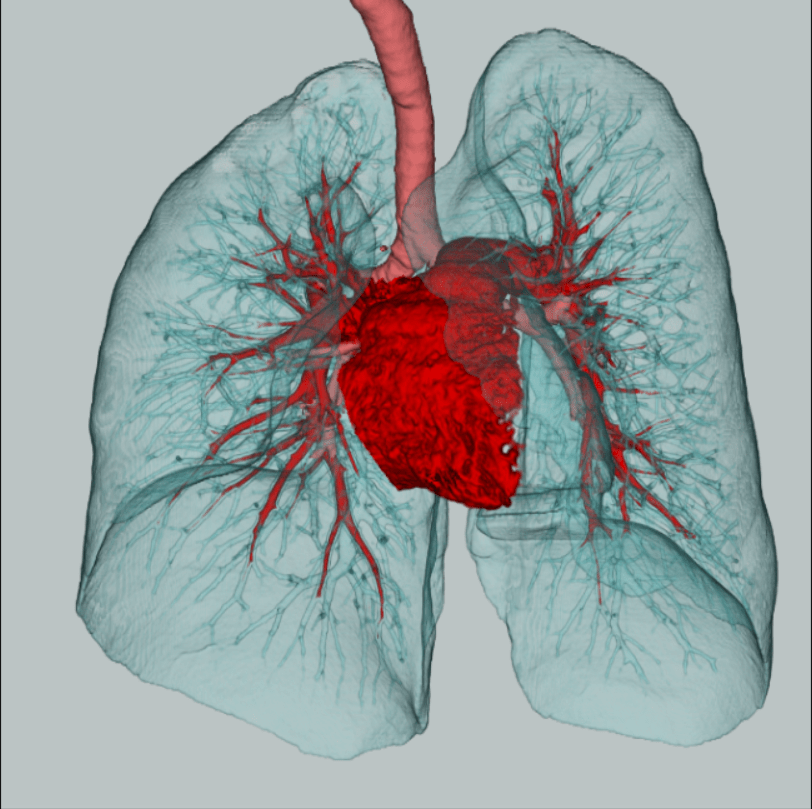

A tomografia de tórax é o melhor exame para análise do pulmão, pois dispõe de imagens mais nítidas e de alta qualidade, sendo indicada para identificação de várias patologias que atingem o parênquima pulmonar, caixa torácica, auxiliando na avaliação de anormalidades pleurais e mediastinais.

A tomografia de tórax de alta resolução realiza cortes milimétricos do parênquima pulmonar, permitindo avaliações extremamente precisas da situação dos pulmões. É o melhor método por imagem para o estudo detalhado de patologias pulmonares, contribuindo muito para a identificação mais específica de suas causas.